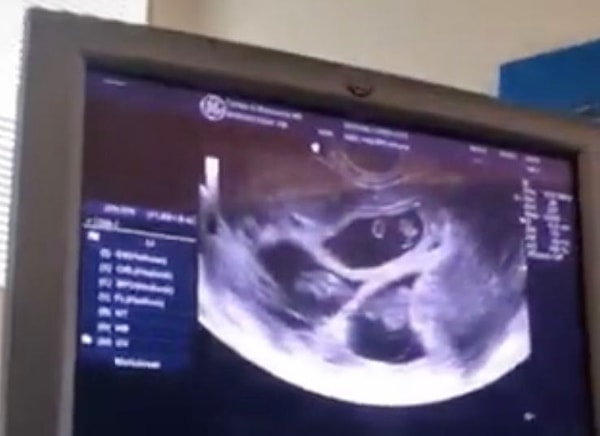

«Мой врач делает мне УЗИ каждые две недели, чтобы подтвердить, что это суперфетация, а не просто двойная абсорбция или недоедание. Но теперь мой третий ребенок в порядке. Мы не пользовались защитой, потому что я уже была беременна во время полового акта с мужем».

«Мои первые два ребенка на 10-11 дней старше третьего. Так мы поняли о моей второй беременности».